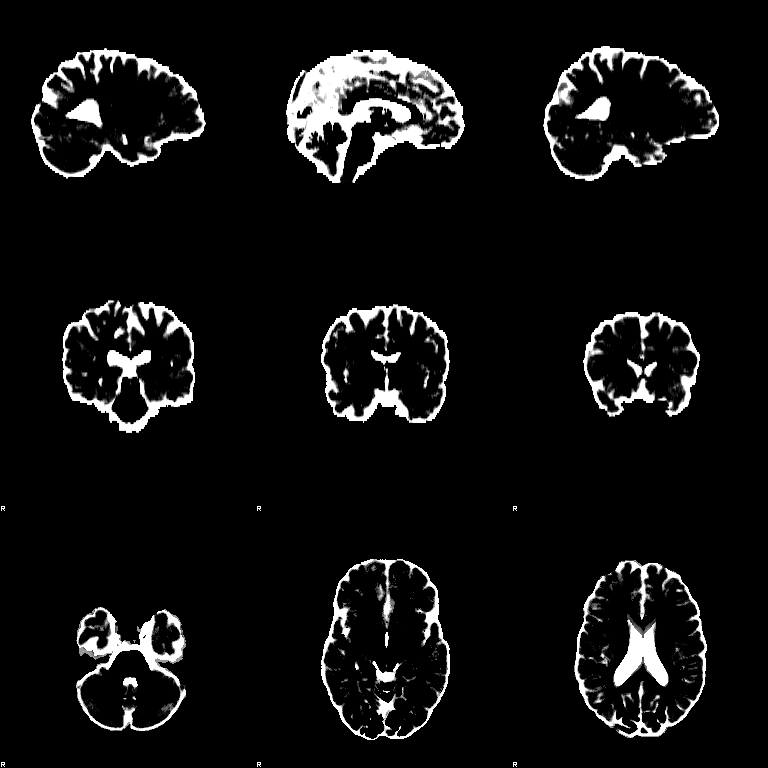

FAST

Set the Input image to be structural_brain (i.e. it is important to have run BET first). Turn on the Partial volume maps optional output images. Press Go. The outputs will be structural_brain_seg, structural_brain_pve_0, structural_brain_pve_1 and structural_brain_pve_2.